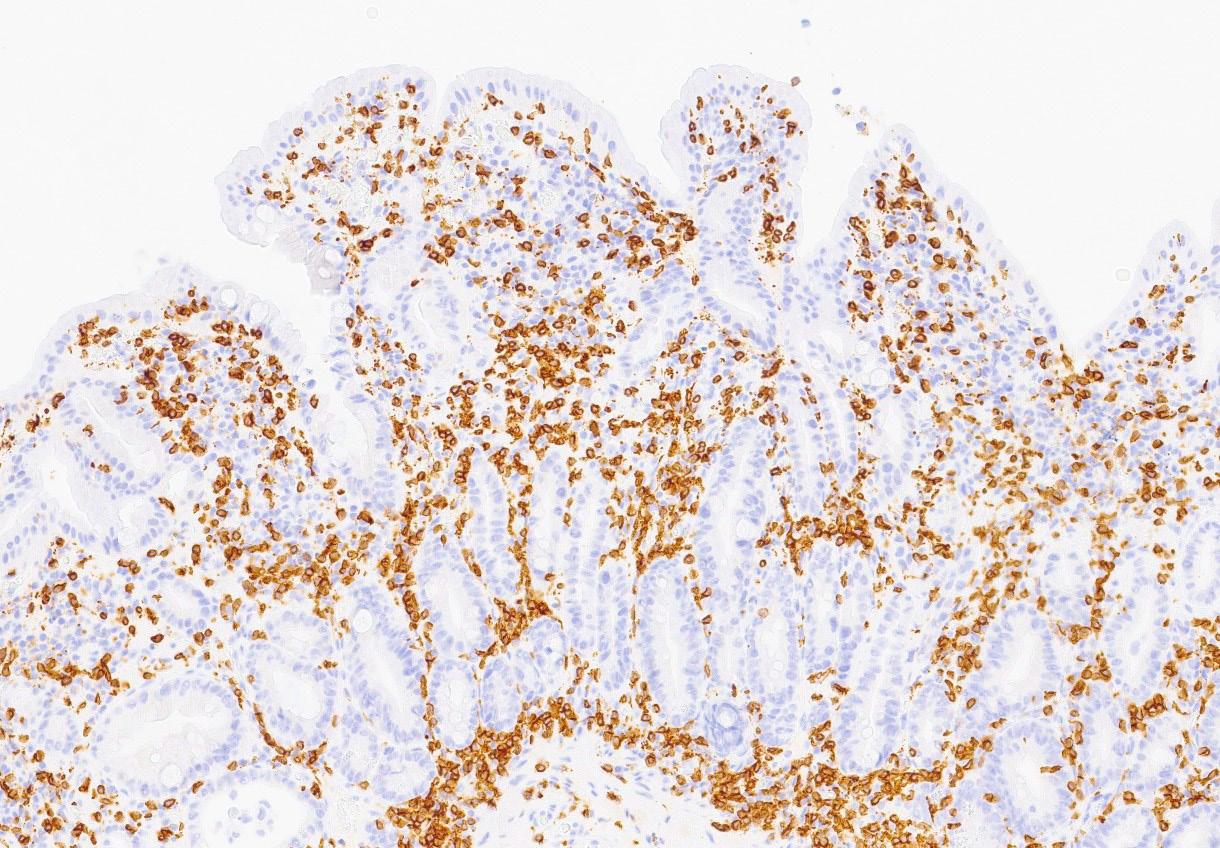

Det ble da også tatt biopsier fra terminale ileum, som viste moderat totteatrofi og kronisk betennelse. Duodenalbiopsi viste totteatrofi og økt antall intraepiteliale lymfocytter (bilde 1 og 2) tilsvarende cøliaki Marsh grad 3b. Anti-TG2 var negativ og hun hadde normal total IgA. MR av tynntarm viste normale forhold.

Bilde 2: (CD3, 300x) Fra syk fase. Immunhistokjemisk undersøkelse viser betydelig økt antall CD3-positive T-lymfocytter i overflateepitelet.